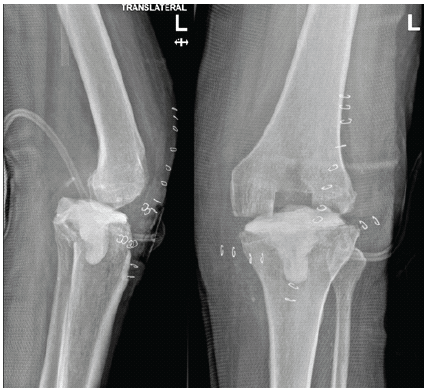

He underwent radical resection, the implant was removed, and a local cement spacer was implanted (Fig. 2).

Figure 2. Left knee after implant removal and spacer insertion. Anteroposterior and lateral radiographs showing removal of the prosthetic components and placement of an antibiotic-loaded cement spacer as part of first-stage infection management.

A prolonged course of delayed wound healing, superficial cast-related sores, and progressive loss of motion occurred in the post-operative period. The mild anterior dislocation was evident on X-ray, and Ilizarov fixation was initially suggested. However, due to persistent infection, poor soft-tissue envelope, significant bone loss, delayed wound healing, and the patient’s multiple comorbidities, including diabetes and peripheral vascular disease, reimplantation was deemed high risk. After multidisciplinary discussion, knee arthrodesis was selected as a definitive salvage procedure to achieve infection control and limb stability. The patient subsequently underwent knee arthrodesis using external fixation, with successful fusion and resolution of infection. Final radiographs confirmed solid fusion of the left knee without evidence of recurrent infection (Fig. 3).

Figure 3. Left knee after arthrodesis. Anteroposterior radiograph demonstrating successful left knee arthrodesis with solid fusion following definitive salvage management for persistent prosthetic joint infection.